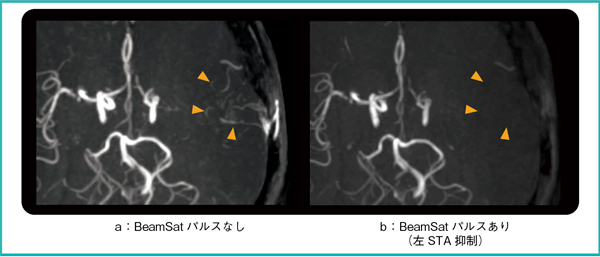

最後に,左浅側頭動脈(STA)-MCAバイパス術の術後評価に適用した結果を図8に示す。図8 aに示した通常の3D TOF画像で左MCA領域に血流信号が確認できるが,バイパスを介した血流が描出されているのか,左ICAからの血流が描出されているのかの詳細な血行動態は判断が難しい。ここで,BeamSatパルスを左STAに印加した図8 bにおいて,左MCA領域が抑制されていることから,左MCAはSTAからバイパスを介した血流であることが確認できる。

以上に示した結果より,ウィリス輪やバイパスを介した頭部の複雑な血行動態を描出可能であることがわかった。

図8 臨床画像3:左STA-MCAバイパス手術後

a:左MCA領域の血流信号が確認できる(▶)。

b:左MCAが抑制されており,左MCAは左STAからバイパスを介した血流であることが確認できる。